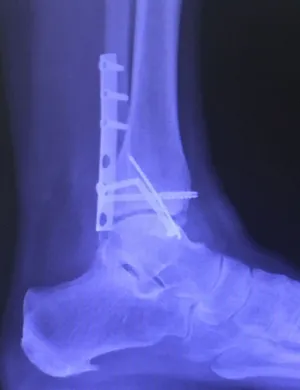

Below are x-rays of a foot pre-operatively (left) where the black line indicates and plantarflexed (downward directed) talus bone and post-surgical repair with a subtalar joint implant and lenthening of the calf muscle which allows the calcaneus (heel bone) to set underneath the talus and the implant keeps the talus from subluxing off the calcaneus and now the talus is more inline with the front of the foot (right).